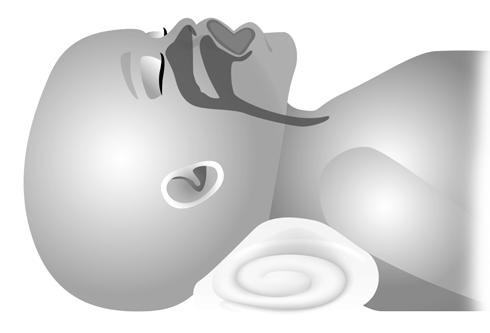

6. O passo mais importante é a visualização das cordas vocais (Figura 6.1.1):

Figura 6.1.1 – Visualização das cordas vocais (figura a cores na página do livro em https://materiais.lidel.pt/neonatologia_procedimentos_tecnicos).